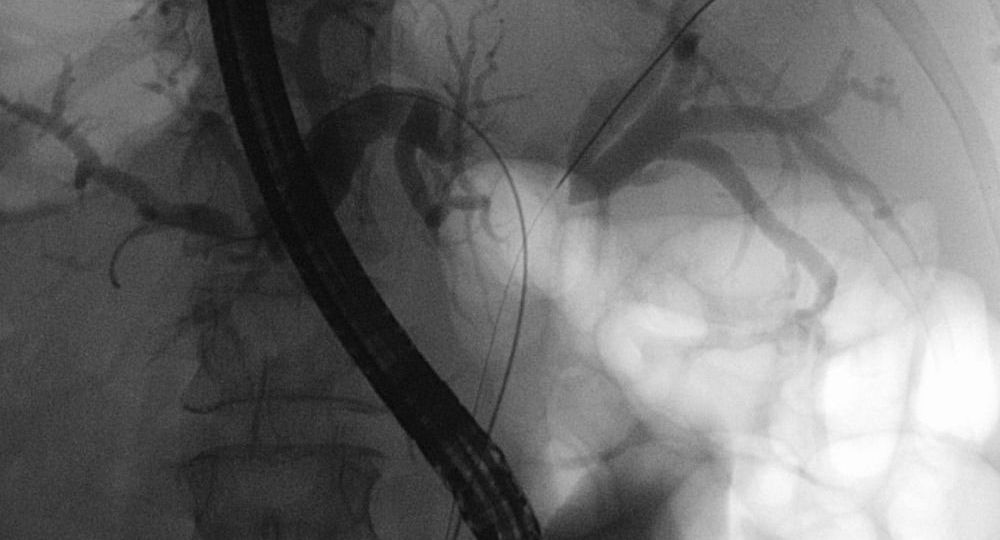

1. Introduction to Klatskin Tumor 1.1 Definition and Characteristics Klatskin tumor is a specific type of cholangiocarcinoma that develops at…

1. Understanding Bile Duct Cancer Bile duct cancer (cholangiocarcinoma) can develop in both intrahepatic (within the liver) and extrahepatic (outside…

1. Introduction to Bile Duct Cancer Bile duct cancer is classified based on its location: This cancer may grow slowly…

1. Introduction to Bile Duct Cancer (Cholangiocarcinoma) Bile duct cancer refers to a group of cancers that originate in the…